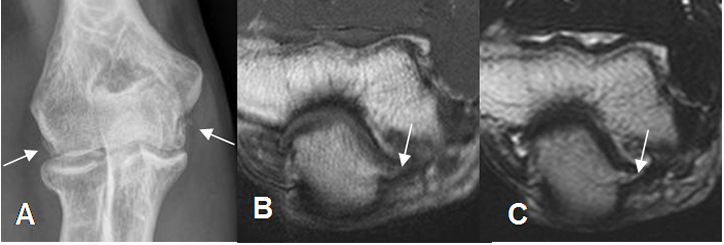

Fig 54 A. Compresión del nervio ulnar.

A: Rx AP. Formación de osteofitos, por enfermedad degenerativa.

B: RM axial en T1 y C: RM axial en T2. Osteofitos dirigidos hacia el canal del ulnar, con pérdida de la grasa, por compresión del nervio.